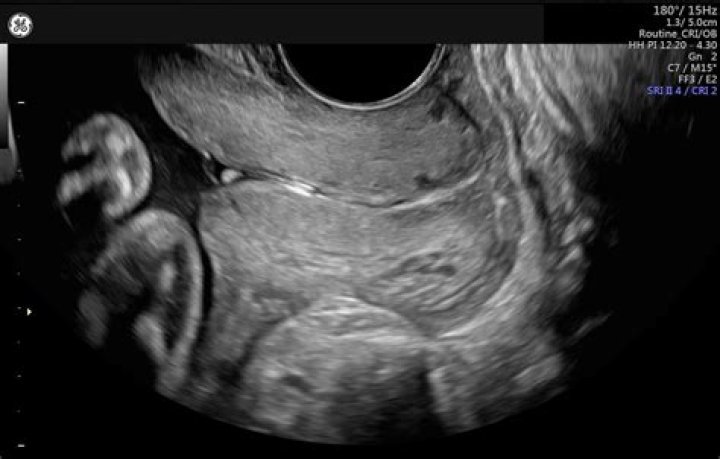

Cervical length refers to the length of the lower end of your uterus. During pregnancy, the length of the cervix might shorten too soon, increasing the risk of preterm labor and premature birth.